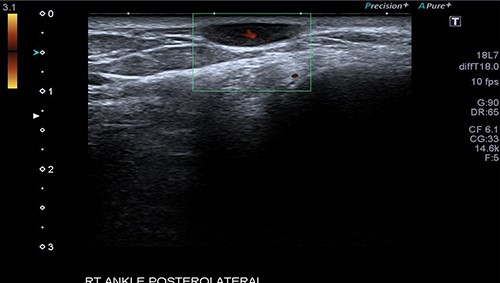

A 34-year-old gentleman presented with a swelling over the posterolateral aspect of his right ankle close to the Achilles tendon. He complained of pain and sensitivity to wearing shoes. The swelling was 10 × 5 mm, mobile and ultrasound (US) scan reported it as ‘A well-defined ovoid hypoechoic lesion underneath the skin surface measuring approximately 11 mm × 3 mm in diameter and appears related to a linear hypoechoic structure’ (Fig. 1). ‘The lesion is slightly heterogeneous in texture and shows posterior acoustic enhancement on the underlying tissues. There is mild internal vascularity of this lesion on Doppler assessment’ (Fig. 2) and ‘these appearances are suggestive of superficial neuroma lesion’. Post-excision, the histology of a single piece of pale smooth firm tissue (9 × 6 × 5 mm) was reported as angioleiomyoma. He made an uneventful recovery and was discharged after 4 months of follow-up.

The Doppler US image of the right ankle posterolateral aspect of Patient 1, which shows mild internal vascularity.

An arteriogram or Doppler study may be useful to an extent, but a confirmed diagnosis is only obtained through histopathological examination after excision [8–10]. Case 1 had an US scan of the swelling which showed a well-defined ovoid hypoechoic lesion underneath the skin surface, and the lesion was slightly heterogeneous in texture and shows posterior acoustic enhancement on the underlying tissues. There was mild internal vascularity of this lesion on Doppler assessment—appearances suggestive of superficial neuroma lesion. The usual appearance of these lesions on USS is a well-circumscribed oval mass with a homogenous echotexture and occasionally hypoechoic protrusions.